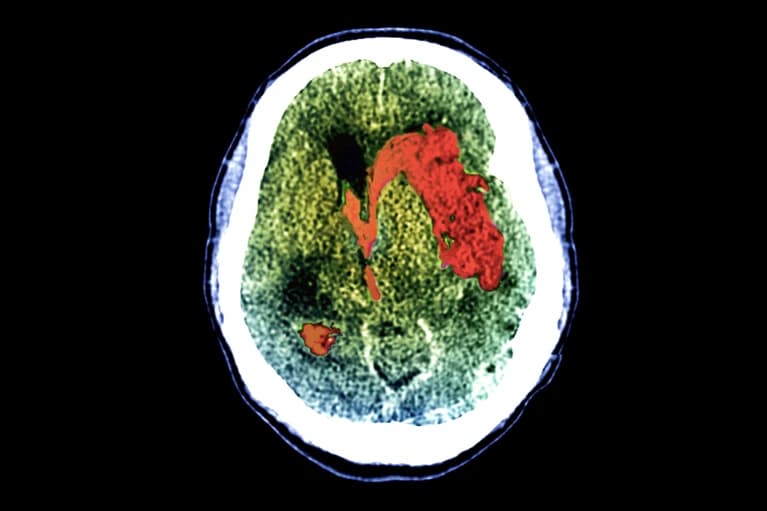

18moStudy Reveals 25% of Unresponsive Brain-Injured Patients Are Conscious

- Groundbreaking international study shows 1 in 4 'unresponsive' brain injury patients are actually conscious

- Brain scans revealed mental responses to commands in physically unresponsive patients